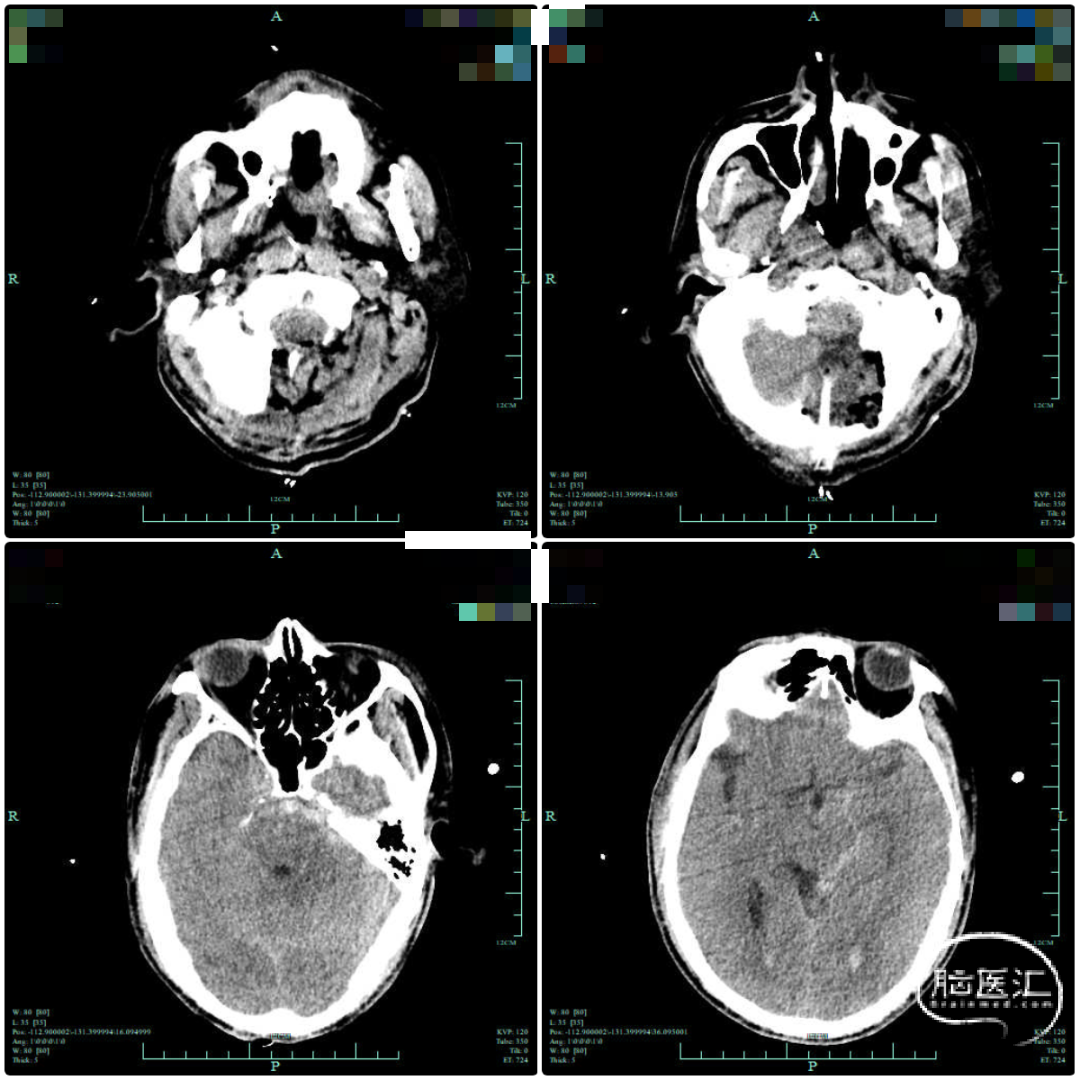

术后复查颅脑CT